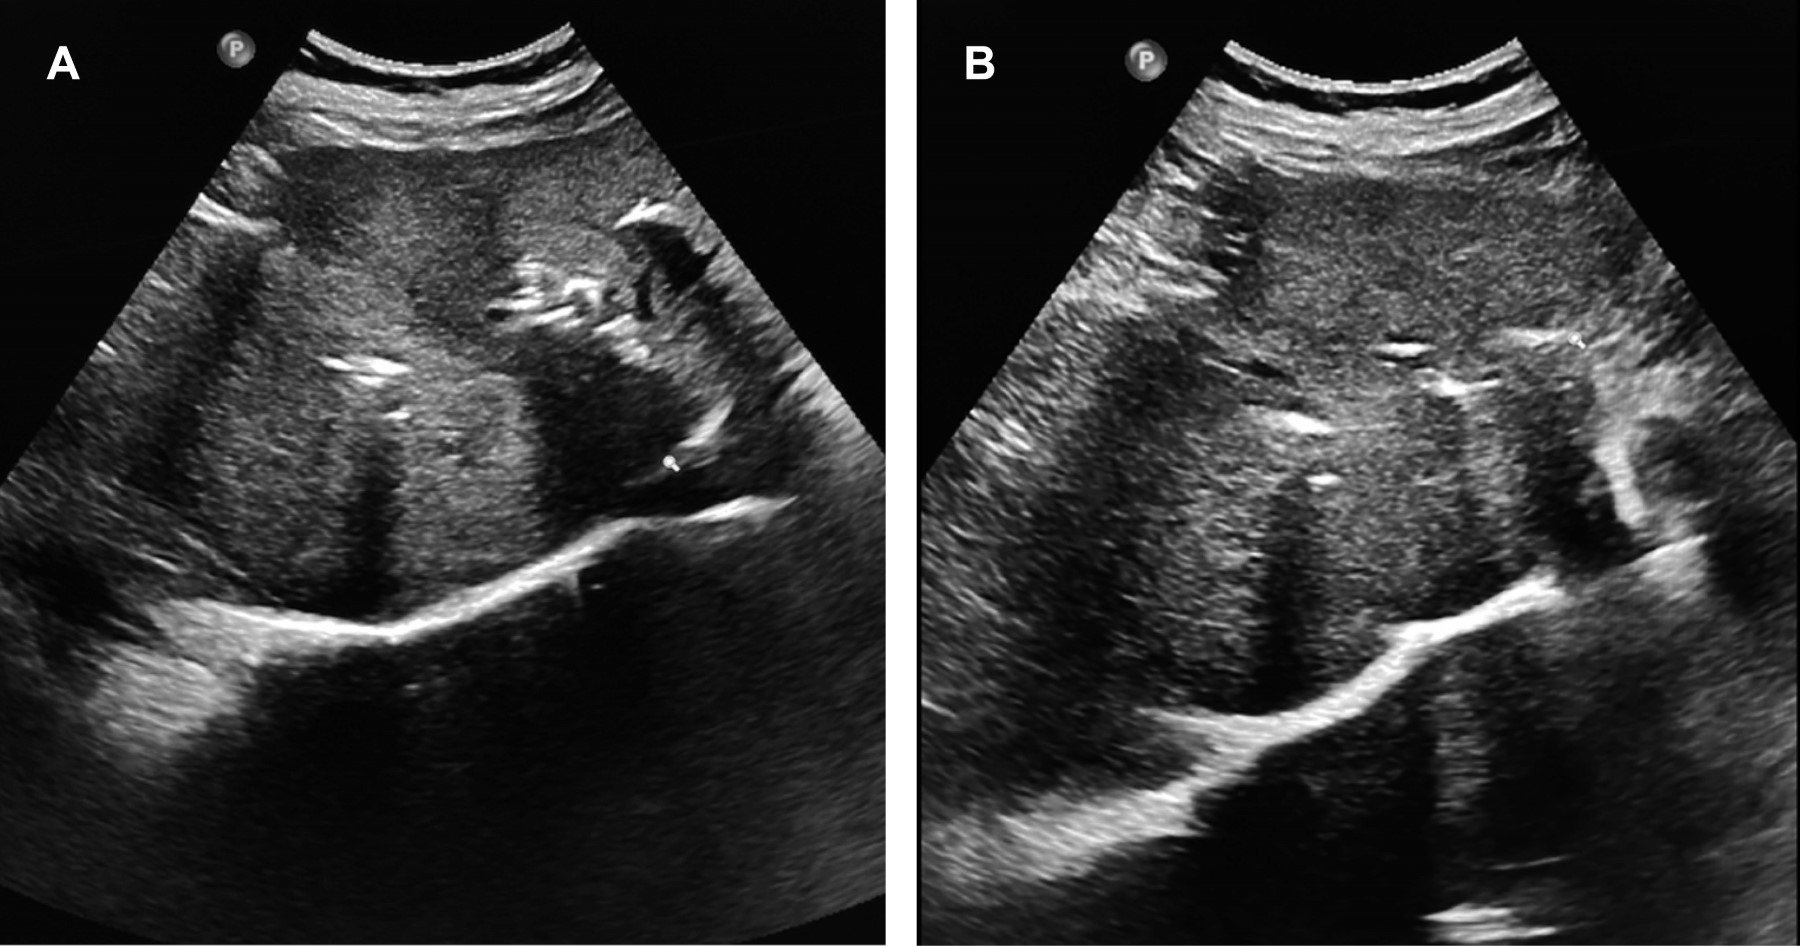

La apariencia del absceso varía según la etapa de desarrollo. En la etapa temprana, es una lesión semisólida ecogénica, heterogénea con límites poco claros y realce posterior de los ecos. El absceso ya formado genera imagen líquida redonda, contornos regulares o irregulares, rodeada por una corona hiperecoica. La identificación de ecos internos corresponde a desechos necróticos, burbujas de gas o refleja la viscosidad de la colección, puede aparecer un nivel hidrolíquido.

El patrón ultrasonográfico del absceso hepático por Klebsiella pneumoniae son bordes irregulares relacionados con licuefacción parcial, con material purulento, lo que se relaciona con su consistencia sólida y por múltiples lóculos que no se comunican (Figura 1).2,3

Figura 1